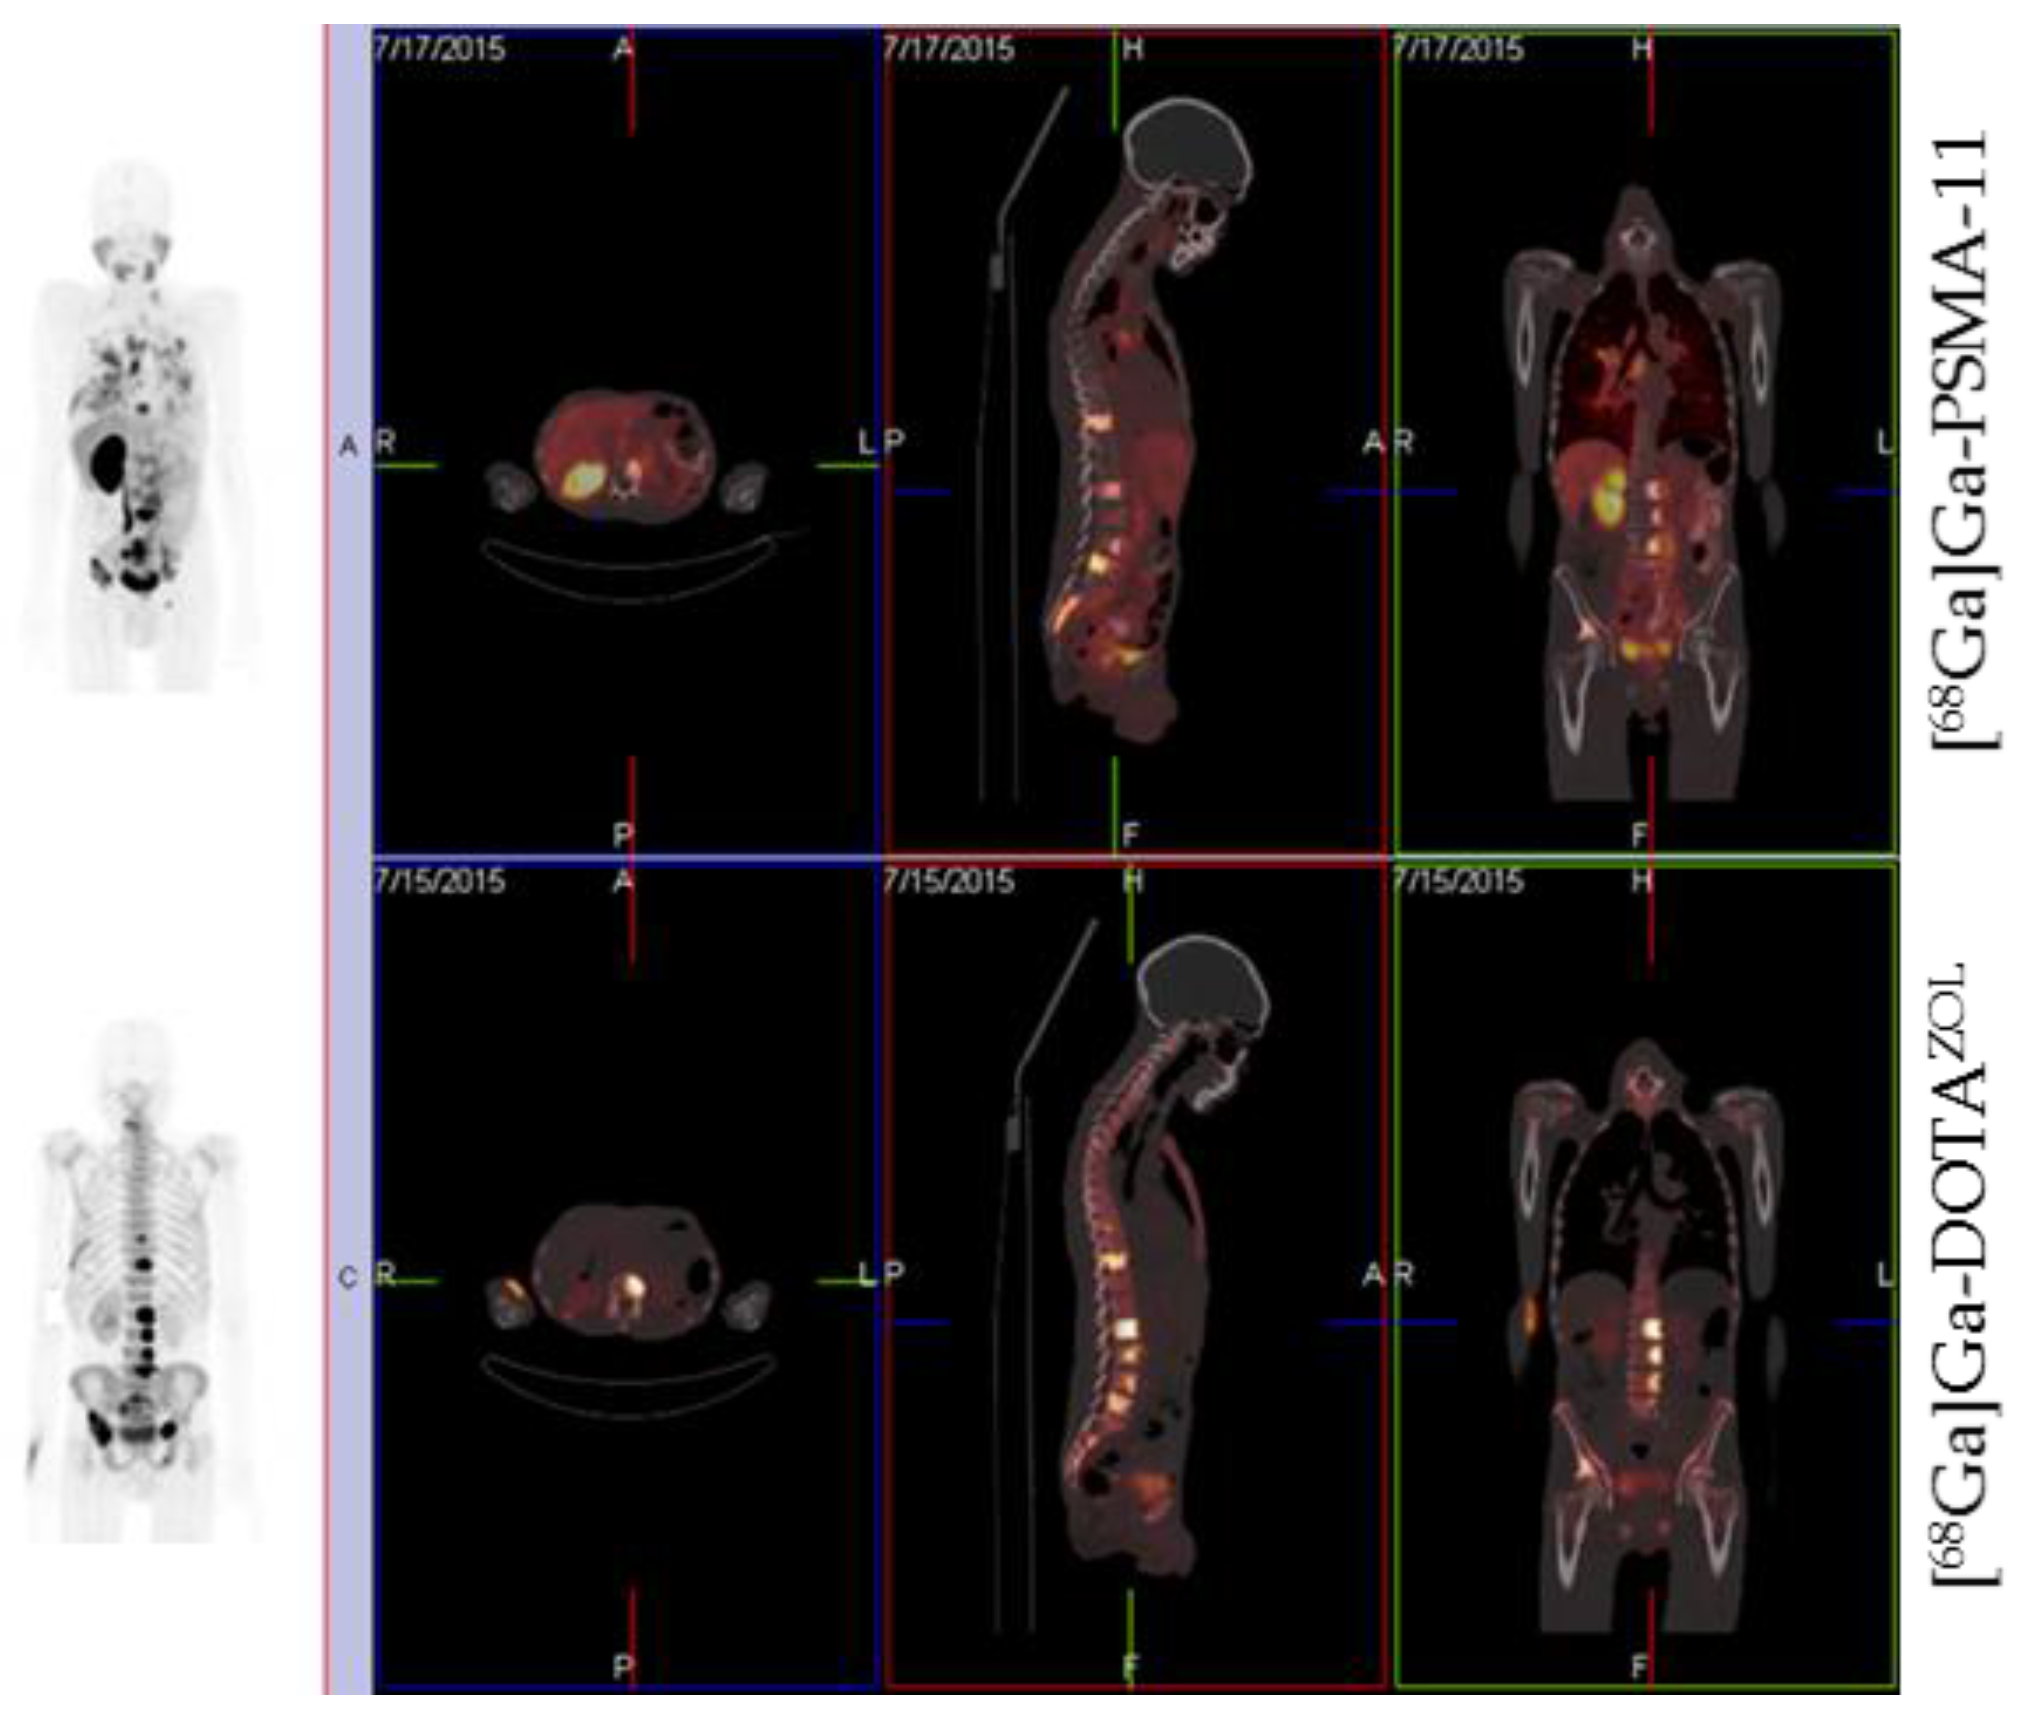

- Fellner, M.; Baum, R.P.; Kubíček, V.; Hermann, P.; Lukeš, I.; Prasad, V.; Rösch, F. PET/CT imaging of osteoblastic bone metastases with 68Ga-bisphosphonates: First human study. Eur. J. Nucl. Med. Mol. Imaging 2010, 37, 834. [Google Scholar] [CrossRef]

- Rösch, F.; Baum, R.P. Generator-based PET radiopharmaceuticals for molecular imaging of tumours: On the way to Theranostics. Dalton Trans. 2011, 40, 6104–6111. [Google Scholar] [CrossRef] [PubMed]